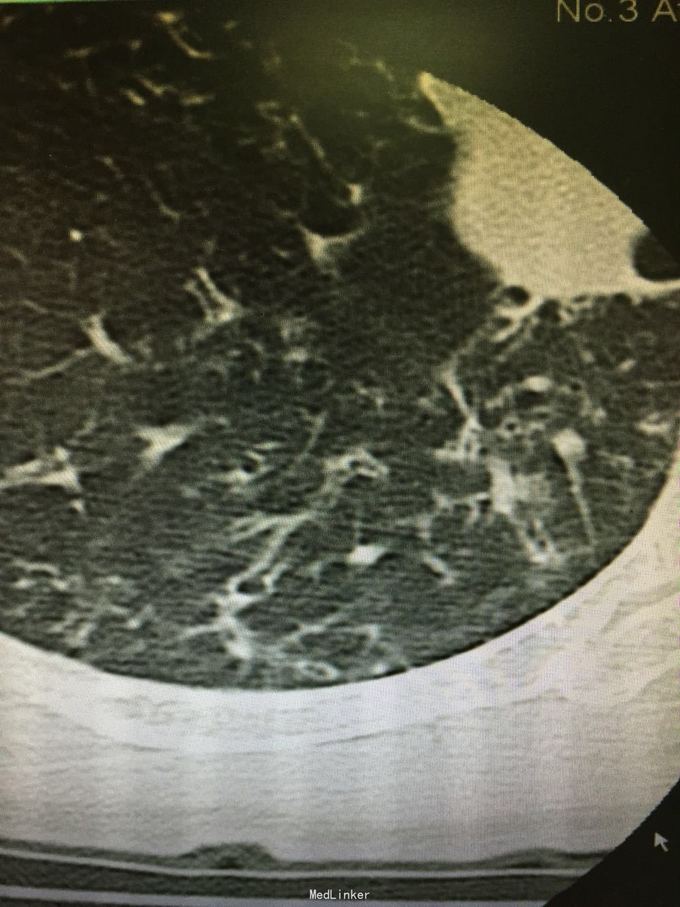

查体:双肺呼吸音粗,双上肺可闻及哮鸣音,双下肺可闻及干湿性罗音。外院胸片示两上中肺可见片装阴影,密度不均匀,边缘模糊,左中肺病灶中可见一椭圆形透光区,大小1.5*2.0cm;双肺纹理增粗、紊乱。考虑继发性肺结核(III上/上中。进展)我院胸片考虑支气管扩张。

肺结核患者易并发支气管扩张。该患者影像学表现为碎饼干渣样,为较典型结核播散灶。支气管扩张表现也较典型。